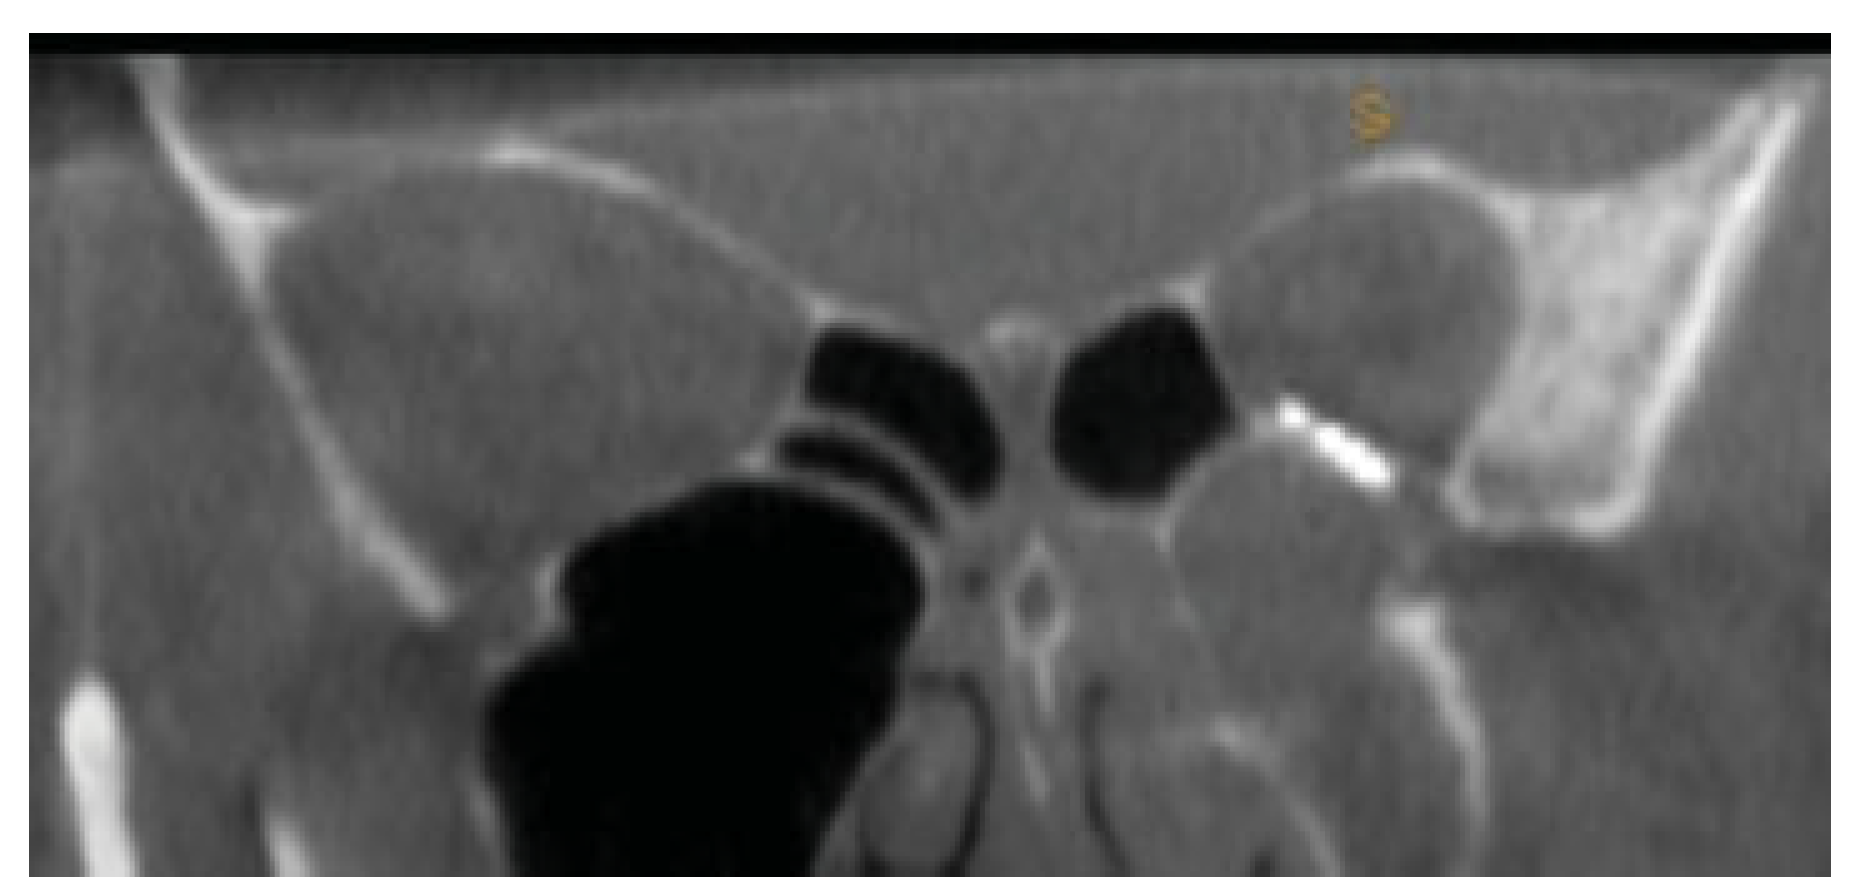

A 59-year-old female presented to the maxillofacial outpatient department following a mechanical fall resulting in a left orbital floor fracture. Enophthalmos of 2 mm was present and a CT scan revealed a large floor defect (Figure 2 and Figure 3). Diplopia was present on upward gaze. A rapid prototyping model was fabricated and a Synthes titanium orbital plate was further adapted preoperatively. The orbital floor was accessed via a mid-lid approach and the modified titanium orbital plate was inserted. No further adaptation of the plate was required and the time taken from insertion of the plate to final fixation was less than 1 minute, as no further adaptation was necessary. Position was confirmed with an intraoperative CT scan (O-arm, Medtronic [Medtronic, Minneapolis, MN]) (Figure 4, Figure 5 and Figure 6). The patient’s diplopia and enophthalmos had resolved 2 weeks postoperatively and no complications were noted at the 6th week follow-up.

Figure 4.

Intra-operative coronal CT scan of posterior ledge and precise relationship to the titanium implant.

Figure 5.

Coronal view with correct adaptation of the plate at medial aspect of the inferior orbital fissure.

Figure 6.

Intraoperative coronal computed tomographic imaging of orbital plate from Case 1.